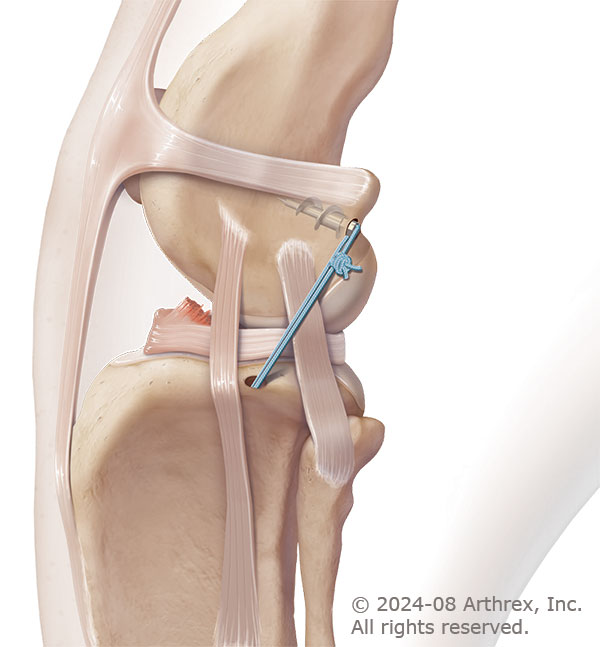

The Anchor Lock surgery utilizes an implanted anchor in the femur bone to securely fixate a suture at points biomechanically similar to the CCL. This prosthetic material has been used with success in human joint stabilizing procedures and provides the temporary stabilization necessary for scar tissue to form and provide long term joint stability.

During the Anchor Lock surgery an anchor implant is placed on the back of the femur bone to fixate a special suture. A tunnel is drilled through the tibia bone and the suture is run through the tunnel and around a surgical button.

The suture is tightened to pull the bones into alignment and tied to hold the knee in place.

Photos courtesy of Arthrex Vet Systems. © 2024-08 Arthrex, Inc. All rights reserved.